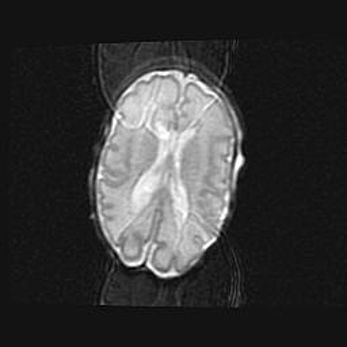

Множественные кисты обоих полушарий головного мозга, наибольшая из них в правой затылочной области. Ассиметричная атрофическая гидроцефалия.

Возраст: 7 месяцев

Вес: 5660 г

Пол: мужской

Окружность головы: 41,5 см

Срок гестации: 28-29 недель

Кисты головного мозга развиваются в результате многоочаговых некрозов вещества мозга и возникают вследствие перенесенной перинатальной инфекции, менингитов, энцефалитов, асфиксии, родовой травмы, расстройств мозгового кровообращения различного генеза. Образованию кист в веществе головного мозга плодов и новорожденных способствуют такие факторы, как высокое содержание в нем воды, недостаточная (или отсутствие) миелинизация и слабая астроглиальная реакция на повреждение.

Кисты могут сочетаться с гидроцефалией и другими поражениями головного мозга.